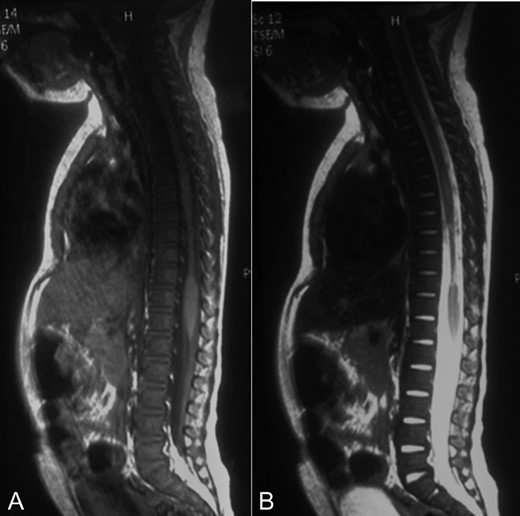

MRI showed a narrowing lesion of the spinal cord from T7 to T10 (Figs 1B, 2A and B).

A-B: A. Sagittal T1 sequence showing a narrowed spinal cord from T7 to T10. B. Sagittal STIR-weighted MRI of the thoracic spine showing chronic appearance of a string-like atrophic cord.